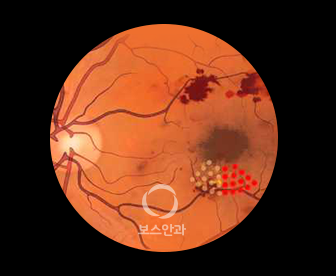

망막 모세혈관이 작은 풍선처럼 커져 꽈리모양으로 변형됩니다.

하지만 모세 혈관벽이 약해서 물이 새어나가게 되면 황반이 붓게되어

망막혈관이 폐쇄 및 손상됨에 따라 신생혈관이 망막에서 유리체를 향해

자라게 합니다. 신생혈관은 약해서 쉽게 터지고 혈액이 누출될 수 있으며,

섬유 조직과 함께 자라난 신생혈관이 수축하여 망막박리 현상이 나타날 수 있습니다.

망막에 수백 개의 응고 반점을 만드는 치료법입니다. 유리체 출혈이나 망막박리에 의한 실명 위험성을 줄일 수 있습니다.

황반부종의 원인이 되는 누출 혈관을 레이저로 응고시켜 시력 악화를 방지하는 치료 방법입니다.